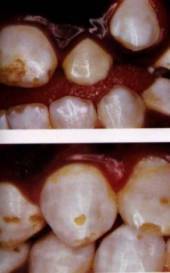

Six types of fluorosis (Source: Fluoride Free, Ireland):

• Type 1: [Top] The earliest sign of dental fluorosis is thin white lines running across tooth. [Bottom] The tips of teeth are white and opaque.

• Type 2: [Top] Unsightly white lines are more defined and are thicker. [Bottom] The tooth shows cloudy areas or thick opaque bands. Greater enamel damage.

• Type 3: [Top] Brown stain superimposed on white cloudy areas. Brown stain equals enamel loss. [Bottom] Entire tooth is opaque and cloudy white. There is complete loss of translucency.